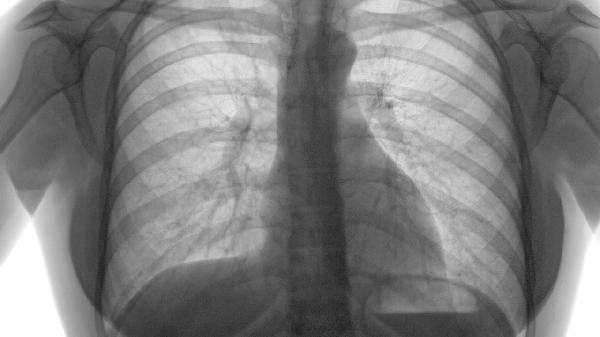

照肺部CT一般不需要空腹,但若需同時進行腹部增強CT檢查則需空腹。肺部CT檢查主要針對胸部病變,通常無須特殊準備。

常規(guī)肺部CT檢查對飲食無限制,檢查前可正常進食飲水。檢查過程中需配合技師指令進行屏氣,避免呼吸運動偽影影響圖像質(zhì)量。若僅進行平掃CT,無需注射造影劑,檢查后即可恢復正?;顒?。檢查前應去除頸部及胸部金屬物品,避免產(chǎn)生偽影干擾診斷。